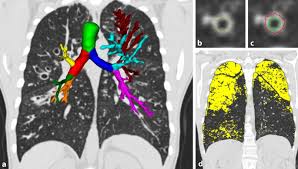

Computertomographie Der Lunge Bei Mukoviszidose Springerlink

Computertomographie Der Lunge Bei Mukoviszidose Springerlink from media.springernature.com